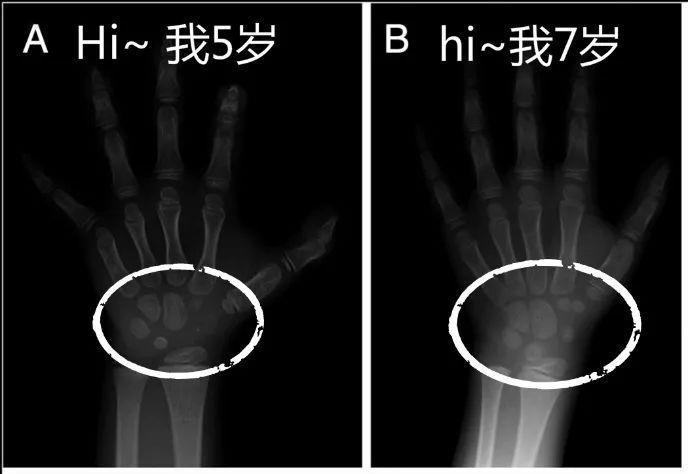

儿童生长发育黄金期,骨龄检测很重要!